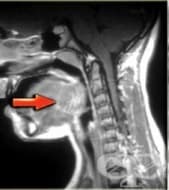

ЯМР на гърло

Гърлото е областта в предната част на шията, обхващаща зоната от подезичната кост до ключицата. В та...